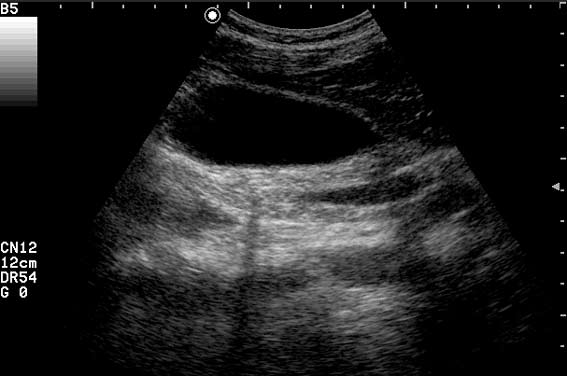

Пациент с приступом резких болей в животе, тошнотой, рвотой.

может это сладж?

"Горошек" в пузыре и холедохе.

Да, ЖКБ, ходедохолитиаз, холецистолитиаз